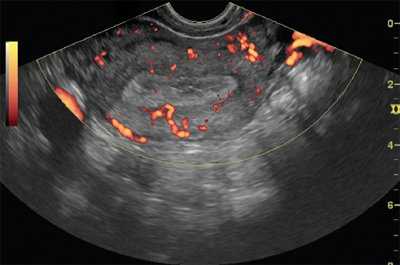

• Цветовая допплерография:

о Множественные питающие сосуды

(Слева) Трансвагинальная цветовая допплерография в поперечной плоскости: визуализируется гиперваскулярное эхогенное объемное образование, растягивающее полость матки, которое по результатам патологического исследования было диагностировано как рак эндометриоидного типа. Прорастание миометрия на УЗИ выявлено не было. Имеется незначительная гематометра.

Интенсивность кровотока зависела от формы роста опухоли: при экзофитной форме отмечен интраопухолевый тип неоваскуляризации, при эндофитной - интенсивный интра- и периопухолевый тип кровотока, богатая васкуляризация миометрия (рис. 1).